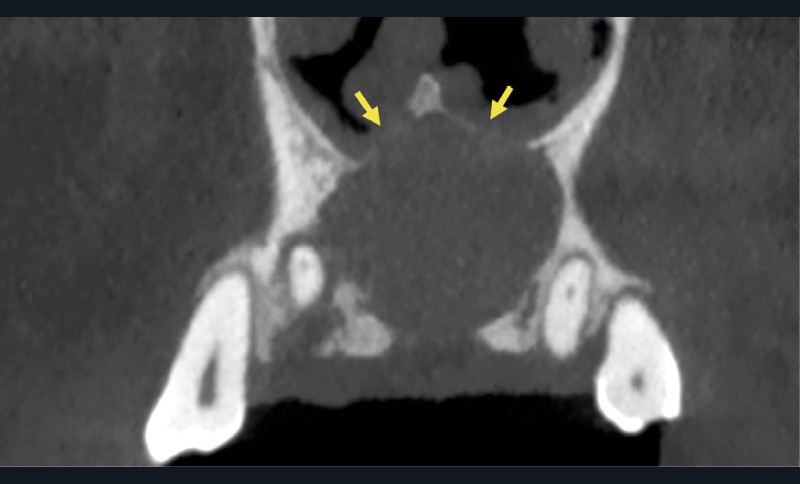

- Lorsque le kyste devient volumineux : possibilité de fenestrer la corticale palatine et/ou vestibulaire. Il peut également se développer dans les fosses nasales ou être associé à des résorptions radiculaires (moins de 25% des cas) (fig. 4).